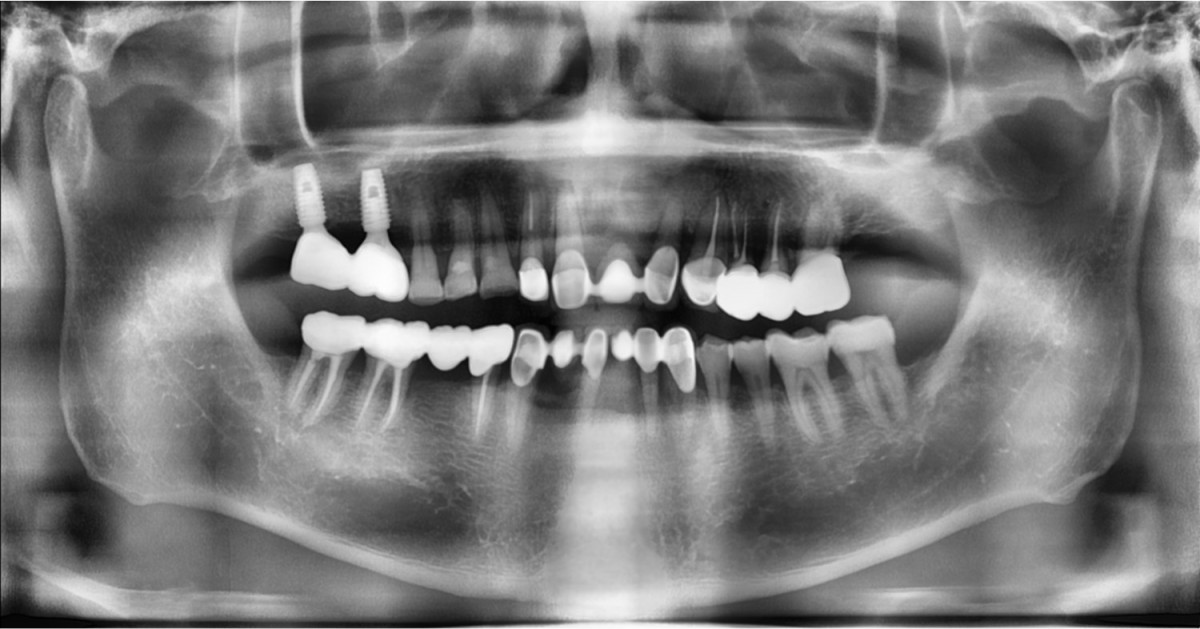

A 57-year-old male patient recently underwent

implant restoration on the maxillary right molar. This time, he is scheduled to

proceed with the left molars. (ARUM implant system)